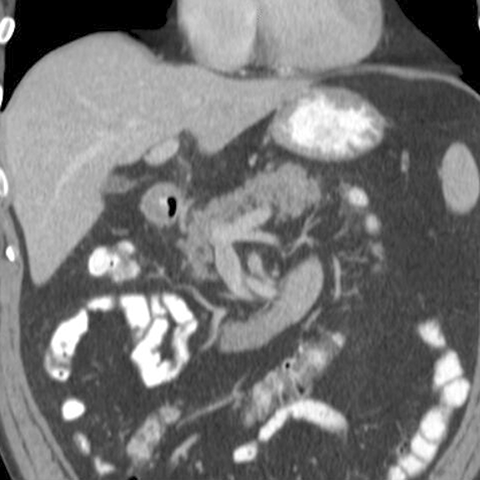

Normal Pancreas, Coronal CT [1 of 3]